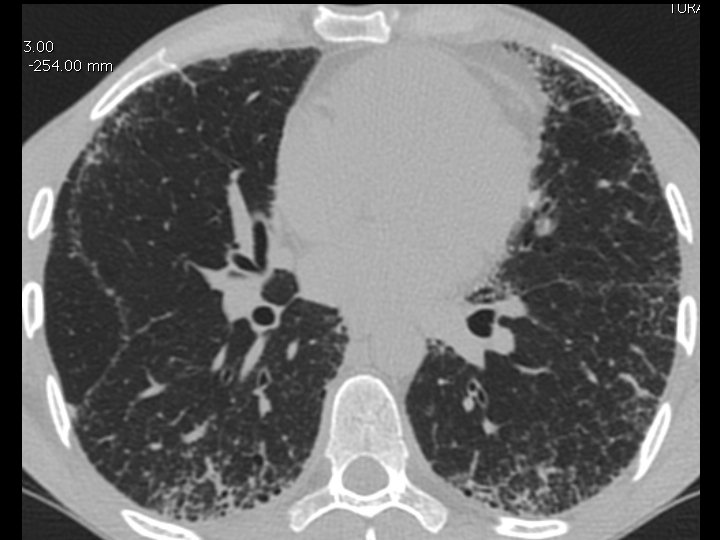

High-resolution CT scan

Subpleural, basal predominance Reticular abnormality Honeycombing with traction bronchiectasis UIPUIP Pattern

Subpleural, basal predominance Reticular abnormality Honeycombing with traction bronchiectasis Profuse micronodules UIPUIP Pattern Inconsistent with UIP Pattern

39 yo caucasian male, works in car collision repair and painting Multiple allergies, Gastroesophageal reflux disease and Thrombocytopenia of unknown etiology Smoker. No drugs CT: Reticular abnormality and honeycombing of subpleural basal predominance + micronodules Lung function tests: decreased diffusion capacity of the lung Blood tests: small increase of ESR and CRP; Autoimmune screening blood tests were normal BAL: normal celularity, with a mild increase in the neutrophil and eosinophil count

39 yo caucasian male, works in car collision repair and painting Multiple allergies, Gastroesophageal reflux disease and Thrombocytopenia of unknown etiology Smoker. No drugs CT: Reticular abnormality and honeycombing of subpleural basal predominance + micronodules Lung function tests: decreased diffusion capacity of the lung Blood tests: small increase of ESR and CRP; Autoimmune Screening Blood Tests were normal BAL: normal celularity, with a mild increase in the neutrophil and eosinophil count Definitive diagnosis can be established? Additional diagnostic tests required? Which tests?